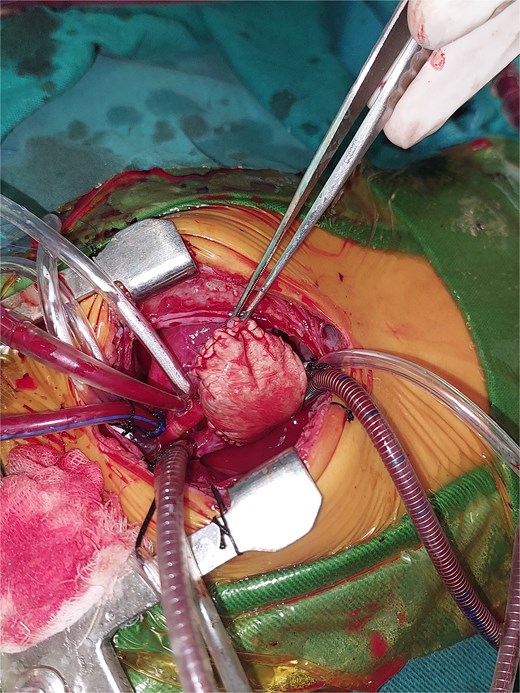

A 2-month-old female infant was admitted with respiratory distress characterized by tachypnea, and cough, along with poor feeding and systemic symptoms such as fever and episodic diaphoresis. At 25 days of age, she had previously been hospitalized for similar symptoms, during which a massive pericardial effusion was identified. Initially, an extracardiac mass was suspected. Despite undergoing two pericardiocenteses and resuscitation after two post-cardiac arrest events, her clinical status continued to deteriorate, and she was referred for urgent surgical intervention due to cardiogenic shock from pericardial tamponade. On examination, she appeared pale with respiratory distress, intercostal retractions, pulsatile hepatomegaly (2 cm), splenomegaly (1 cm), and tachycardia (160 bpm). Laboratory findings showed hyponatremia (125 mmol/L). TTE demonstrated cardiomegaly, bilateral pleural effusion, and a massive pericardial effusion measuring 24–28 mm circumferentially. A 2.7 cm mass adjacent to the anterior RA wall and atrioventricular (AV) groove was identified (Fig. 1). Due to her unstable condition, CT imaging was deferred. An emergent median sternotomy revealed a severely distended pericardium containing copious effusion (Fig. 2). Upon opening the pericardium, immediate hemodynamic improvement was observed. The mass was visualized infiltrating the RA anterior wall and AV groove (Fig. 3). Total cardiopulmonary bypass (CPB) was initiated using aortic and bicaval cannulation. Following cardiac arrest with antegrade cold blood cardioplegia, the RA was incised posterior to the tumour. The lesion extended beyond the AV groove, precluding complete excision due to anatomical constraints (Fig. 4). Subtotal (debulking) resection was performed (Figs 4 and 5), and the RA anterior wall was reconstructed with a bovine pericardial patch (Fig. 6). The patient was successfully weaned from CPB, and the remainder of the surgery was uneventful. The infant was extubated within 48 hours and discharged after a 14-day hospital stay, with subsequent TTE showing satisfactory cardiac function. Histopathological evaluation confirmed a benign capillary hemangioma characterized by lobulated reddish tissue with compact capillary proliferation, fibrous septae, and stromal hyalinization. Immunohistochemical staining was positive for CD31 and CD34, confirming endothelial origin and ruling out malignancy (Fig. 7). At one-year follow-up, the patient remained in excellent general health with no signs of recurrence.

Intraoperative image showing the opened right atrium and the mass partially resected.